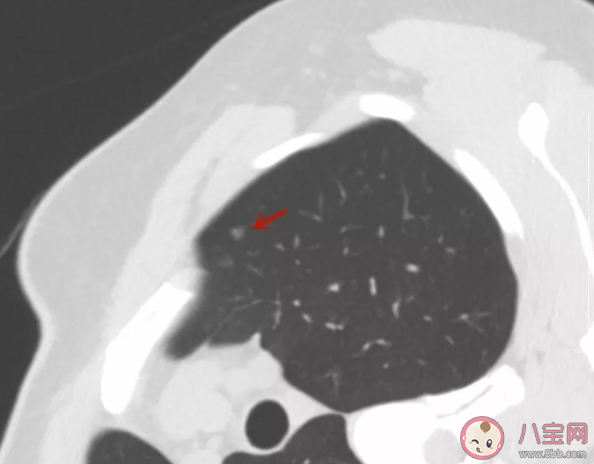

在體檢中發(fā)現(xiàn)肺結(jié)節(jié)讓人非常擔(dān)心是不是肺癌,大多數(shù)情況下的結(jié)節(jié)是良性的,但應(yīng)定期隨訪,肺結(jié)節(jié)和肺癌有什么關(guān)系?為什么發(fā)現(xiàn)肺結(jié)節(jié)的人越來越多?下面八寶網(wǎng)小編就帶來介紹。

肺癌可能長成肺結(jié)節(jié)的樣子,也可能是別的樣子(大腫塊等)。通常情況下,長成肺部小結(jié)節(jié)樣子的肺癌,是癌癥中惡性程度比較低的。

如果結(jié)節(jié)是實性的,大于8mm,那要謹慎抉擇,因為如果是肺癌,將有可能快速進展。

如果結(jié)節(jié)是磨玻璃的,不要慌張,至少間隔三個月隨訪一次是必要的。

如果結(jié)節(jié)位置比較深,位于肺門附近或者肺葉中間,手術(shù)要比較慎重,因為大多數(shù)需要切除一個肺葉。